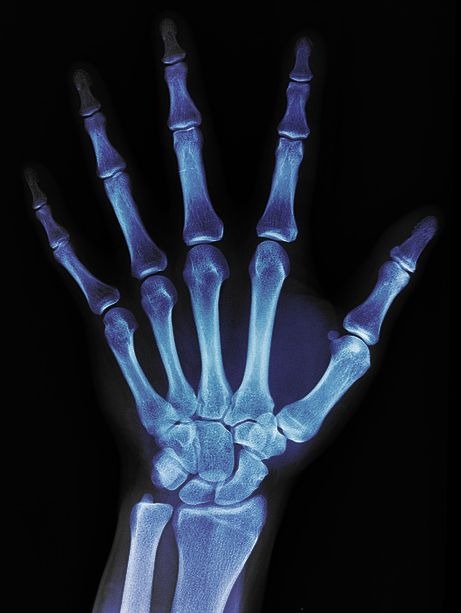

X-Ray Day, also known as the International Day of Radiology (IDOR), is celebrated internationally on November 8th every year, the anniversary of the day X-Rays were discovered in Germany by Wilhelm Conrad Rontgen in 1895. The theme of this years IDOR is Cardiac Imaging, to highlight the increasingly important role of radiologists in cardiac care.